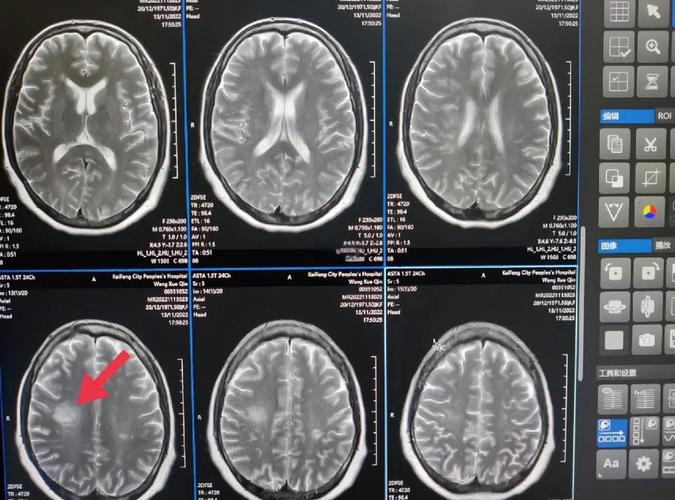

(图片来源网络,侵删)

| MRI (DWI序列) | 看脑组织 | 可以(发病数分钟至1小时内) | 金标准:对早期、超早期的脑梗塞病灶检出率极高,是诊断急性脑梗最敏感的检查。 |